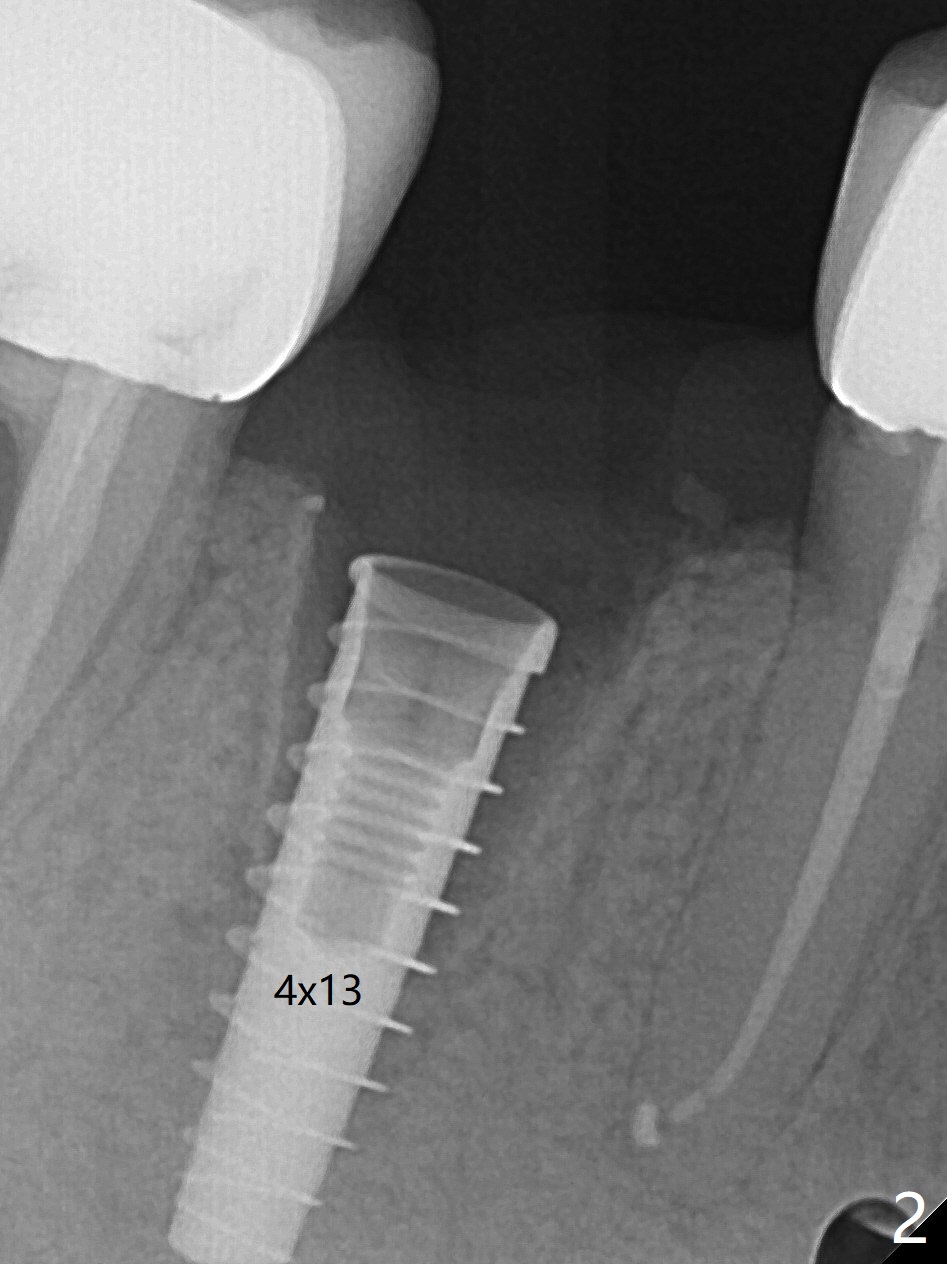

为了准确,这个病例徒手种植需要拍摄8张X光片(这里仅显示其中4张,图一至四),如果采纳导板,2张足够了,而且不担忧神经损伤问题。